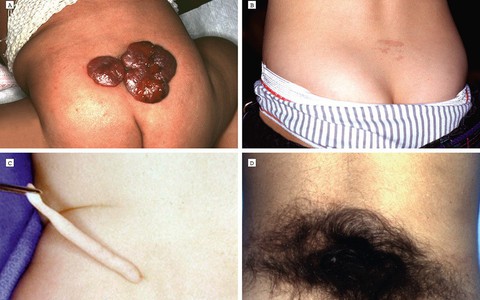

Hội chứng tủy sống bám thấp là một rối loạn thần kinh gây ra bởi tủy sống bị dính với vùng da xung quanh, làm hạn chế sự chuyển động của tủy sống trong cột sống.

TTO - Một phụ nữ 38 tuổi có vòng ngực quá lớn: mỗi bên nặng 1,4-1,5 kg, gấp 5-6 lần so với bình thường vừa được phẫu thuật tạo hình hôm nay 26-6 tại Bệnh viện E.